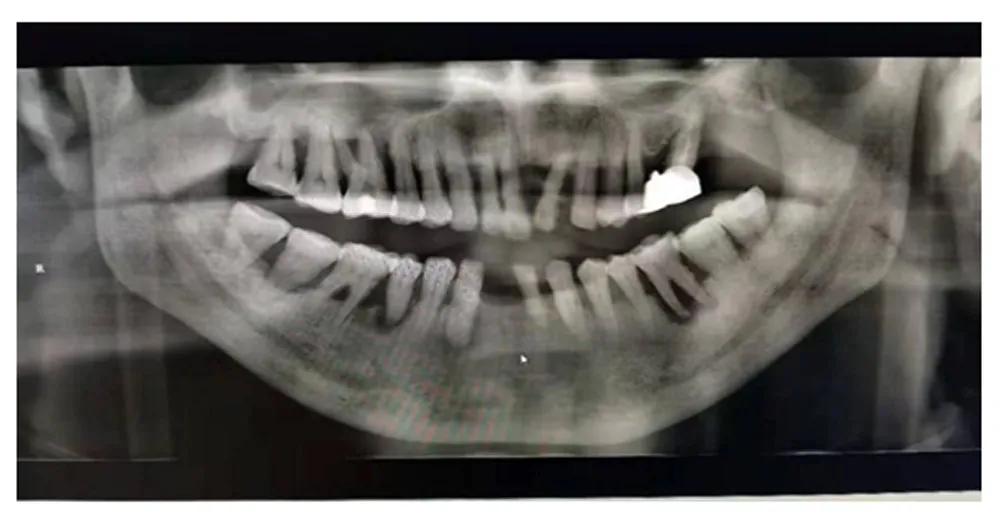

有过看牙经验的人都知道,在一些项目治疗前,牙医会让先拍X光片。牙科常用的X光片主要有三种:小牙片、全景曲断片和牙科CT。今天,我们详细介绍其中一种常用的X光片——全景片。

全景片又称曲面体层片,可以在一张胶片上完整、清晰地显示上颌骨、下颌骨全貌,上下颌牙列情况,牙槽骨情况,能清晰显示上颌窦腔、窦壁、窦底情况,以及颞颌关节情况,并对颌骨周围疾病的诊断提供帮助。

全景片的作用:

全景片可以为医生术前诊断、分析提供全景样图像依据,以便能更好地为患者设计治疗方案,可有如下作用~~

1.牙齿的解剖结构、密度、牙周状况的检查。

2.埋伏牙和智齿的长势、牙根位置和面部神经的距离。

3.牙齿发育情况的判断。

4.牙齿缺失修复前基牙的判断。

5.根管充填、镶牙、种植、矫正的评估及复查。

6.头面部外伤骨折的诊断。